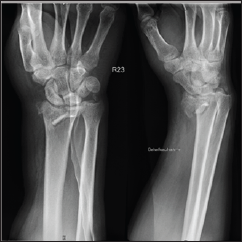

A 48 year-old male, caucasian, policeman, right handed, attended the emergency service due to right wrist pain and functional impotence. Five weeks earlier he had suffered a road accident resulting in a fracture of the distal right radius (AO subtype 23-B3) (Figure 1) and a tibial plafond fracture. At a foreign hospital that received him, he was submitted to radius osteosynthesis with an anatomic volar distal radius plate and in the lower right limb a temporary joint-bridging external fixation was placed during 1 week, and was posteriorly substituted by screws and plate fixation in the tibia and fibula. The wrist cast was removed 4 weeks after surgery in a private hospital in our country. After this episode he began to feel pain, without any history of associated trauma. He had no other previous history of interest. The physical examination revealed a "dinner fork” deformity, with a volar translation of the carpus. The skin was intact. There was no neurovascular deficit. Imaging showed a Dumontier type II volar radiocarpal dislocation (Figure 2A). At the emergency department we conducted closed reduction through traction after infiltration of a local intra- articular anesthetic, without success nevertheless (Figure 2B), so we decided to proceed to surgical treatment. Intraoperatively, through a volar approach of the radius, a bone fragment distal to the plate was visible. A dorsal approach was needed to reduce the dislocation. A radiocarpal fixation with three Kirschner wires was performed, two of them fixing the volar fragment of the distal radius, and one stabilizing the radiocarpal joint. One screw of the plate was removed due to its' intraarticular location. The distal radioulnar joint was evaluated under dynamic fluoroscopy and was apparently stable. Immediate postoperative radiographs confirmed a concentric reduction and stable fixation of the radiocarpal joint (Figure 3). Postoperatively, the patient was placed in an arm cast with free elbow and metacarpophalangeal (MP) joints. There were no perioperative complications. The immobilization and the kirschner wires were maintained for 7 weeks. After removing the cast and the kirschner wires, the patient presented flexion of 20°and extension of 15°, which improved up to flexion 30° and extension 60°, supination 60°, with preserved pronation, 24 months after the trauma. At this time, the patient reports no pain, feeling of instability or signs of nerve compression. The DASH disability score result was 3,1 and the Mayo Wrist Score was 93. The radiograph control did not show any relevant alteration (Figure 4).

Figure 1: Simple AP and lateral radiograph obtained upon arrival at the emergency service at the foreign hospital.